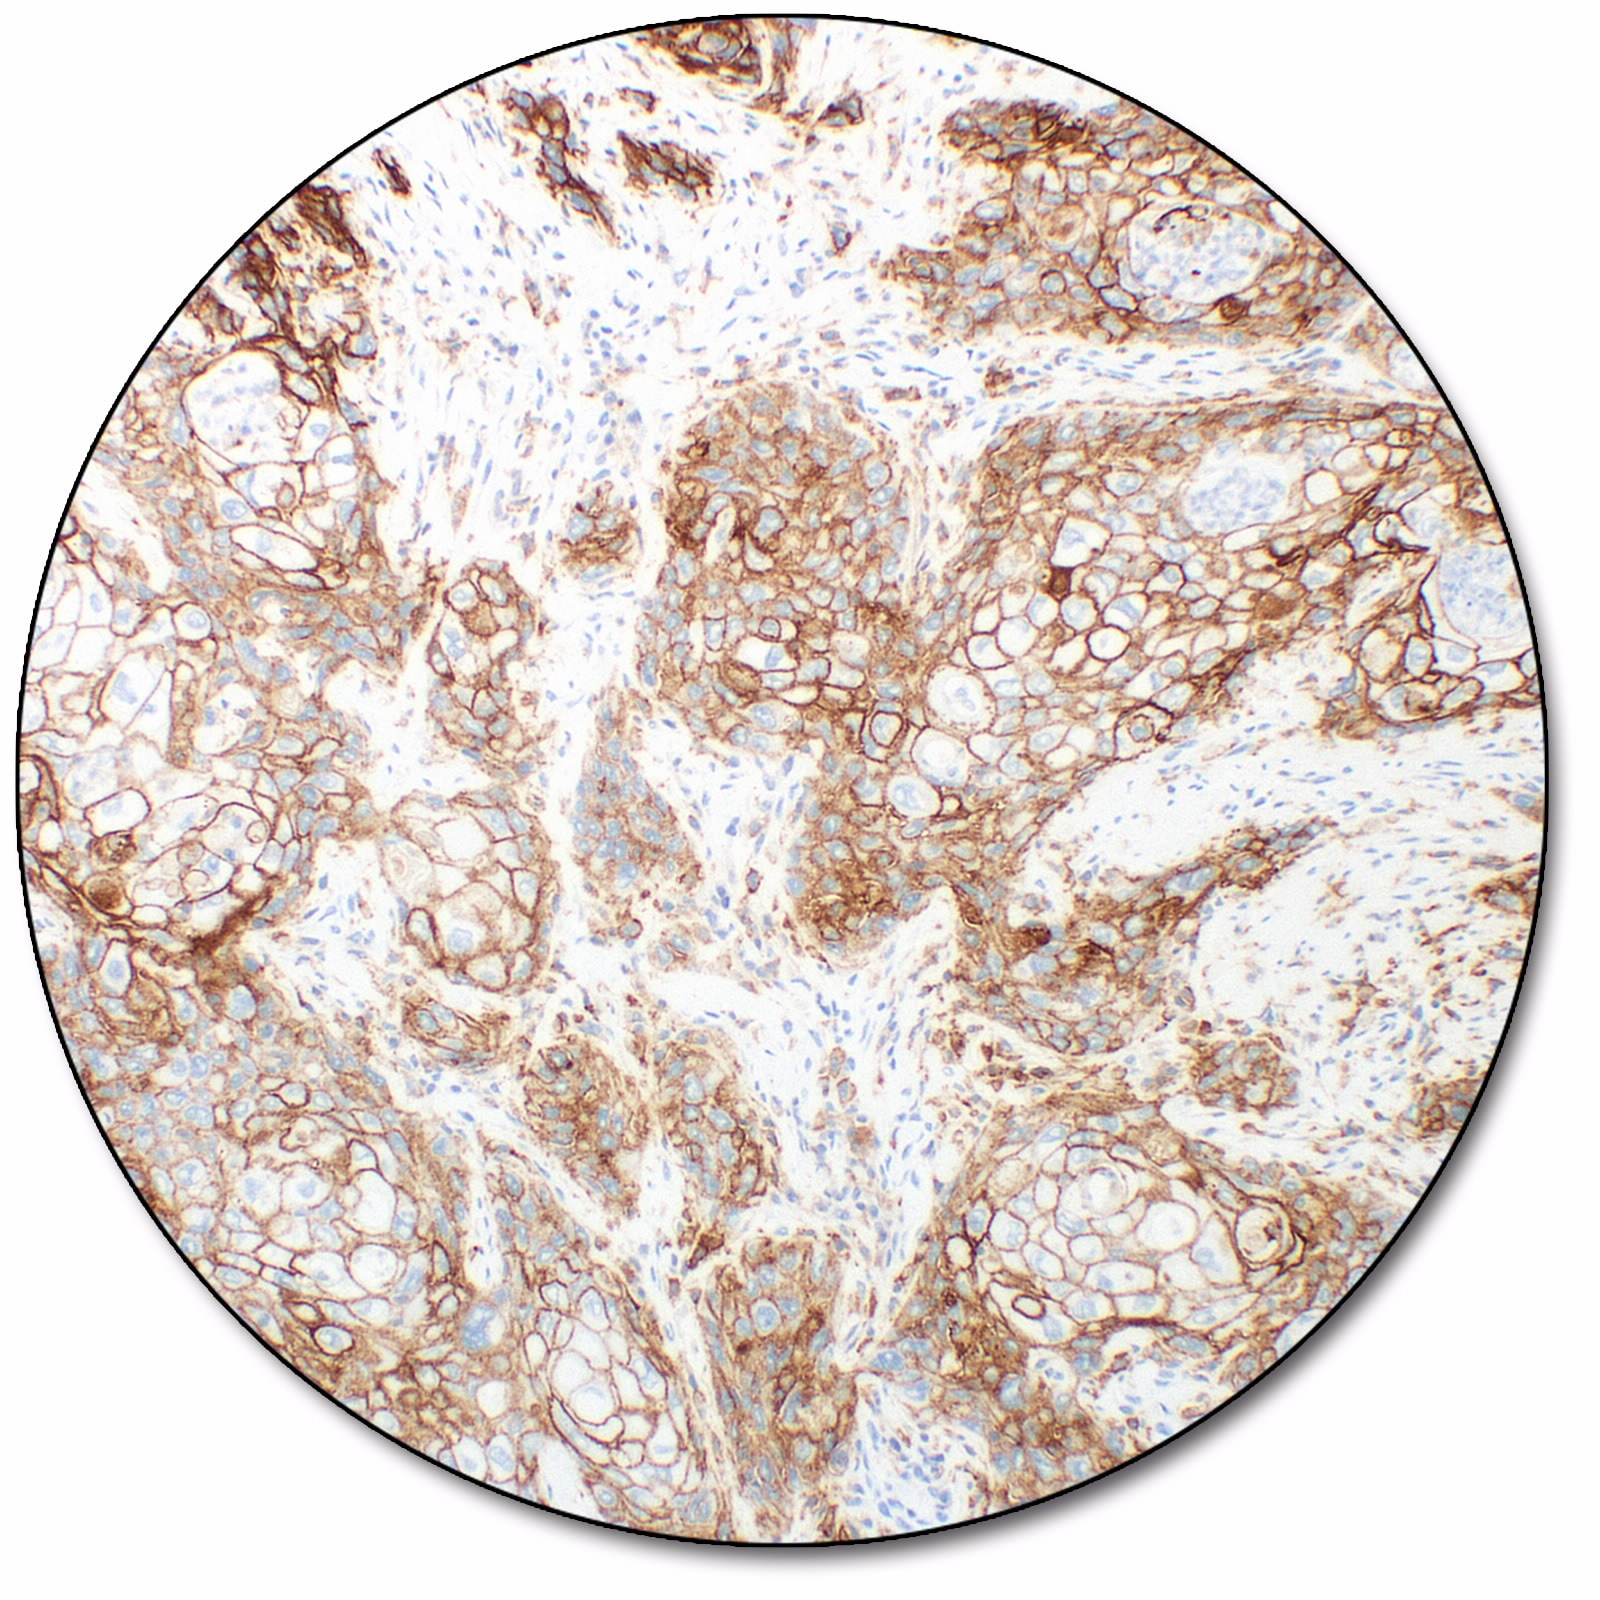

Melanoma

PD-L1 protein expression in NSCLC, non-squamous non-small cell lung cancer (nsNSCLC), melanoma, MIUC, and esophageal squamous cell carcinoma (ESCC) is determined by using % tumor cell expression, which is the percentage of evaluable tumor cells exhibiting partial or complete membrane staining at any intensity.

PD-L1 expression (< 1% tumor cell expression) as detected by PD-L1 IHC 28-8 pharmDx is indicated as an aid in identifying melanoma patients for treatment with Opdualag™ (nivolumab and relatlimab) as a companion diagnostic test.

PD-L1 expression (≥ 1% or ≥ 5% tumor cell expression) as detected by PD-L1 IHC 28-8 pharmDx in melanoma may be used as an aid in the assessment of patients for whom OPDIVO® (nivolumab) and YERVOY® (ipilimumab) combination treatment is being considered.